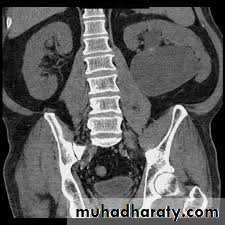

DIAGNOSIS

IVUDIAGNOSIS

CTTreatment

Children may be observed with US and renogram if they remain stable andhave good renal function and no other complications (such as persistent infection or stones).

If children are symptomatic or have a signifi cant hydronephrosis with impaired renal function (<40%), pyeloplasty is recommended